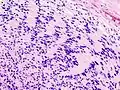

| Micrograph of a schwannoma showing both a cellular Antoni A area (top) and a loose paucicellular Antoni B area (bottom). HE stain. | |

Verocay bodies are seen histologically in schwannomas.

- Cellular schwannoma is a relatively rare variation. Cellular schwannoma is nearly exclusively made up of a fascicular proliferation of well-differentiated Schwann cells that are cytologically bland, missing Verocay bodies, and just slightly exhibiting Antoni B pattern growth (10% of the tumor area).[12][13][14] Local recurrence is Variable (5-40%) and perhaps greater than in normal schwannomas.[15][16]